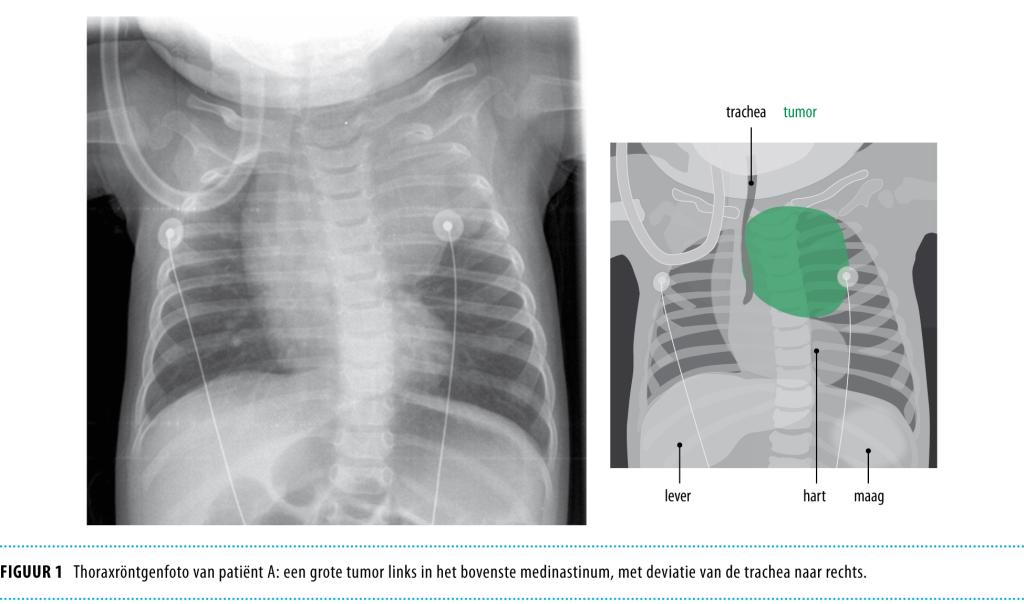

Patiënt F, een jongen van 6 jaar oud, werd gezien vanwege een zachte, niet-pijnlijke massa ter hoogte van het rechter bovenbeen. Een MRI-scan toonde een tumor met een hoge vetdensiteit, verdacht voor een lipoom of een lipoblastoom (figuur 4). Pathologisch onderzoek toonde matuur vetweefsel zonder necrose, hyperchromatische kernen of opvallende mitosen. Er waren geen septa. De vetcellen infiltreerden in het spierweefsel. De bevindingen waren verdacht voor een lipoom, maar de mogelijkheid van een matuur liposarcoom kon niet worden uitgesloten. Cytogenetisch onderzoek toonde een translocatie tussen chromosoom 4 en 12: 46,XY,T(4;12)(p16:q15), wat de diagnose ‘lipoom’ bevestigde (lipomen hebben vaak afwijkingen aan chromosoom 6, 12, of 13). Na 3 jaar follow-up ontstond een recidief-lipoom, dat eveneens werd gereseceerd.

Figuur 4